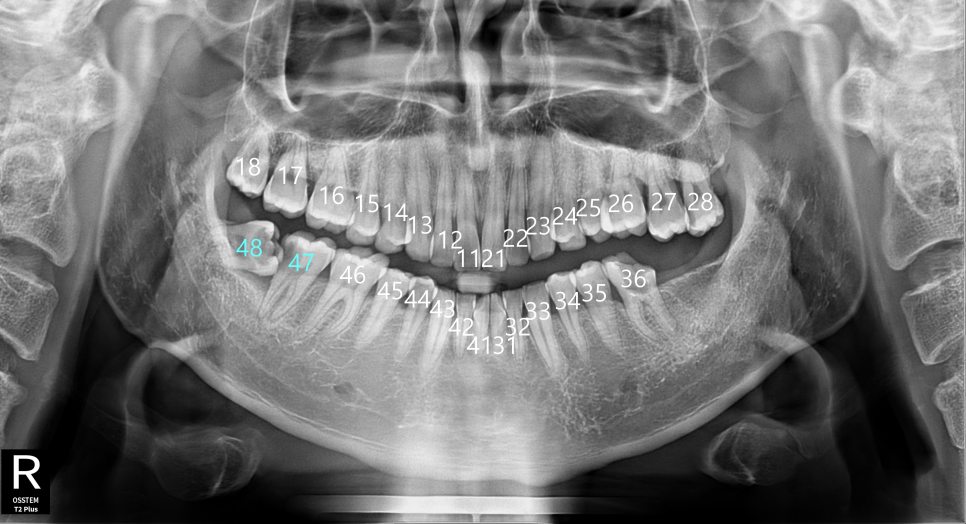

모든 치아에는 각각의 고유 번호가 있습니다.(이미지 참고)

치과에서는 이 치아 번호를 통해 정확히 어떤

치아를 말하는지 빠르게 구분할 수 있습니다.

이번 환자분이 발치 진단을 받았던

가장 큰 원인도 바로 이 48번

즉, 사랑니의 위치 때문이였습니다.

촬영일:2025.07.15 (첫 내원)